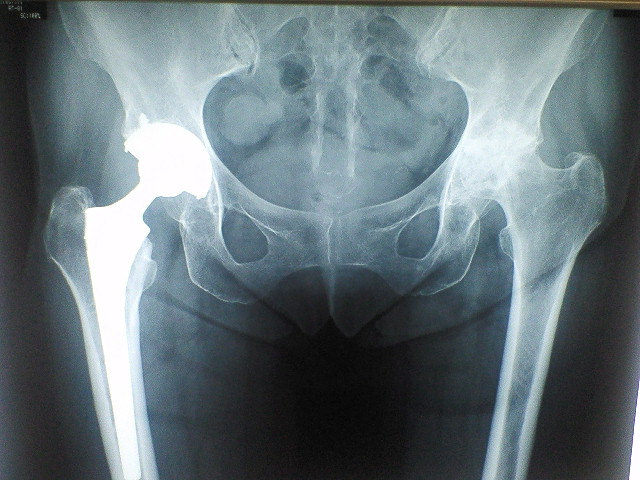

股関節の手術。。

右を手術したのは4年前だった。。

4年前の手術に比べると。。。